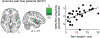

Differences in fMRI resting-state connectivity of the default mode network (DMN) seen in chronic pain patients are often interpreted as brain reorganization due to the chronic pain condition. Nevertheless, patients' pain at the time of fMRI might influence the DMN because pain, like cognitive stimuli, engages attentional mechanisms and cognitive engagement is known to alter DMN activity. Here, we aimed to dissociate the influence of chronic pain condition (trait) from the influence of current pain experience (state) on DMN connectivity in patients with fibromyalgia (FM). We performed resting-state fMRI scans to test DMN connectivity in FM patients and matched healthy controls in two separate cohorts: (1) in a cohort not experiencing pain during scanning (27 FM patients and 27 controls), (2) in a cohort with current clinical pain during scanning (16 FM patients and 16 controls). In FM patients without pain during scanning, the connectivity of the DMN did not differ significantly from controls. By contrast, FM patients with current clinical pain during the scan had significantly increased DMN connectivity to bilateral anterior insula (INS) similar to previous studies. Regression analysis showed a positive relationship between DMN-midINS connectivity and current pain. We therefore suggest that transient DMN disruptions due to current clinical pain during scanning (current pain state) may be a substantial contributor to DMN connectivity disruptions observed in chronic pain patients.